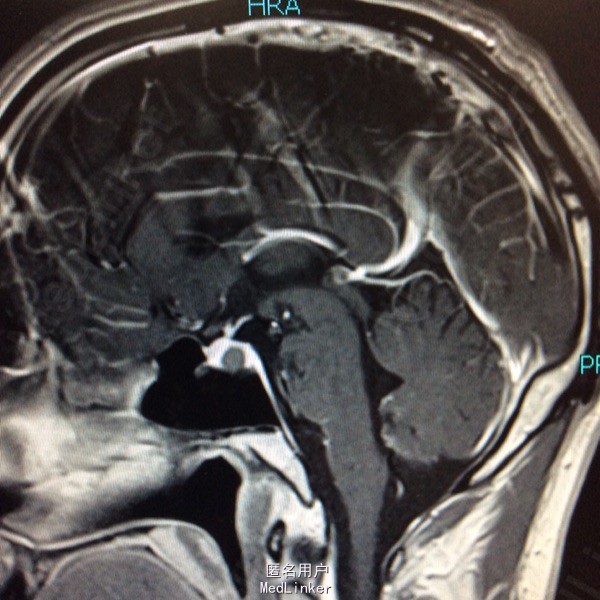

查体未见明显阳性体征,发育正常 头颅CT提示鞍区少量出血 MRI增强提示鞍区占位病变,大小约0.8*1.5cm 考虑垂体瘤卒中

术前诊断:垂体瘤 择期行经蝶入路垂体瘤切除术 术后病理提示垂体腺瘤